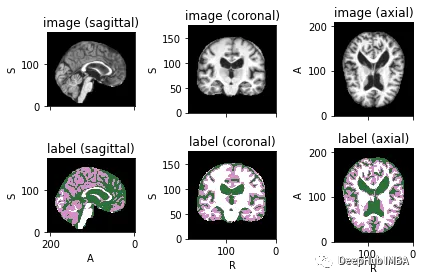

为了可视化带有相应标签的图像,可以使用TorchIO,这是一个Python库,用于深度学习中多维医学图像的加载、预处理、增强和采样。

subject = torchio.Subject(image=torchio.ScalarImage(image_filename), label=torchio.LabelMap(label_filename))

subject.plot()